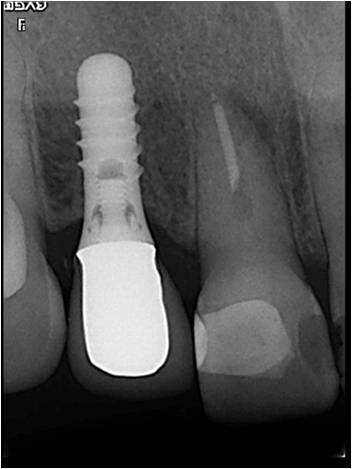

前歯が折れて来られた患者さんです。インプラントの周囲に十分な骨がなかったので、骨を作る為に人工骨を入れました。下写真 怖い人は見ないでください。

しっかり骨の中に埋められています。